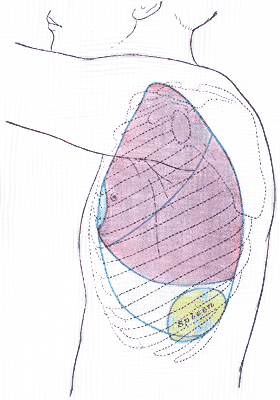

The diaphragmatic surface of the spleen (or phrenic surface) is convex, smooth, and is directed upward, backward, and to the left, except at its upper end, where it is directed slightly to the middle. The spleen lies beneath the left diaphragm, beneath the ninth, tenth, and eleventh ribs. The diaphragm separates the spleen from the pleura and base of the left lung.

Back of lumbar region, showing surface markings for kidneys, ureters, and spleen. Side of thorax, showing surface markings for bones, lungs (purple), pleura (blue), and spleen (green).

Side of thorax, showing surface markings for bones, lungs (purple), pleura (blue), and spleen (green).- Spleen